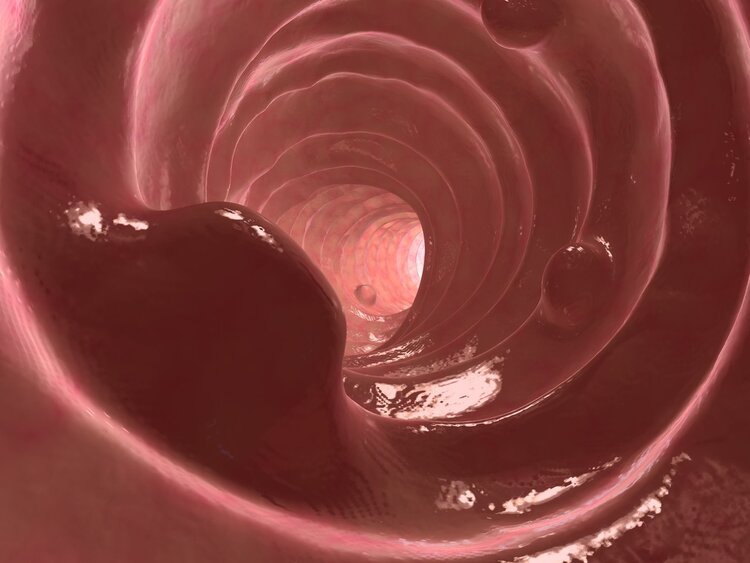

大家常说的肠癌一般指大肠癌,包括结肠癌和直肠癌,是常见的恶性肿瘤。全球范围内,大肠癌发病率、死亡率在全部恶性肿瘤中均位居第5位。

我国大肠癌中约60%为直肠癌,直肠指检可发现60~70%的直肠癌,是简单、经济、有效的检查方法。除此之外,也可以通过内镜检查获得病理诊断,是制定治疗方案的重要依据。